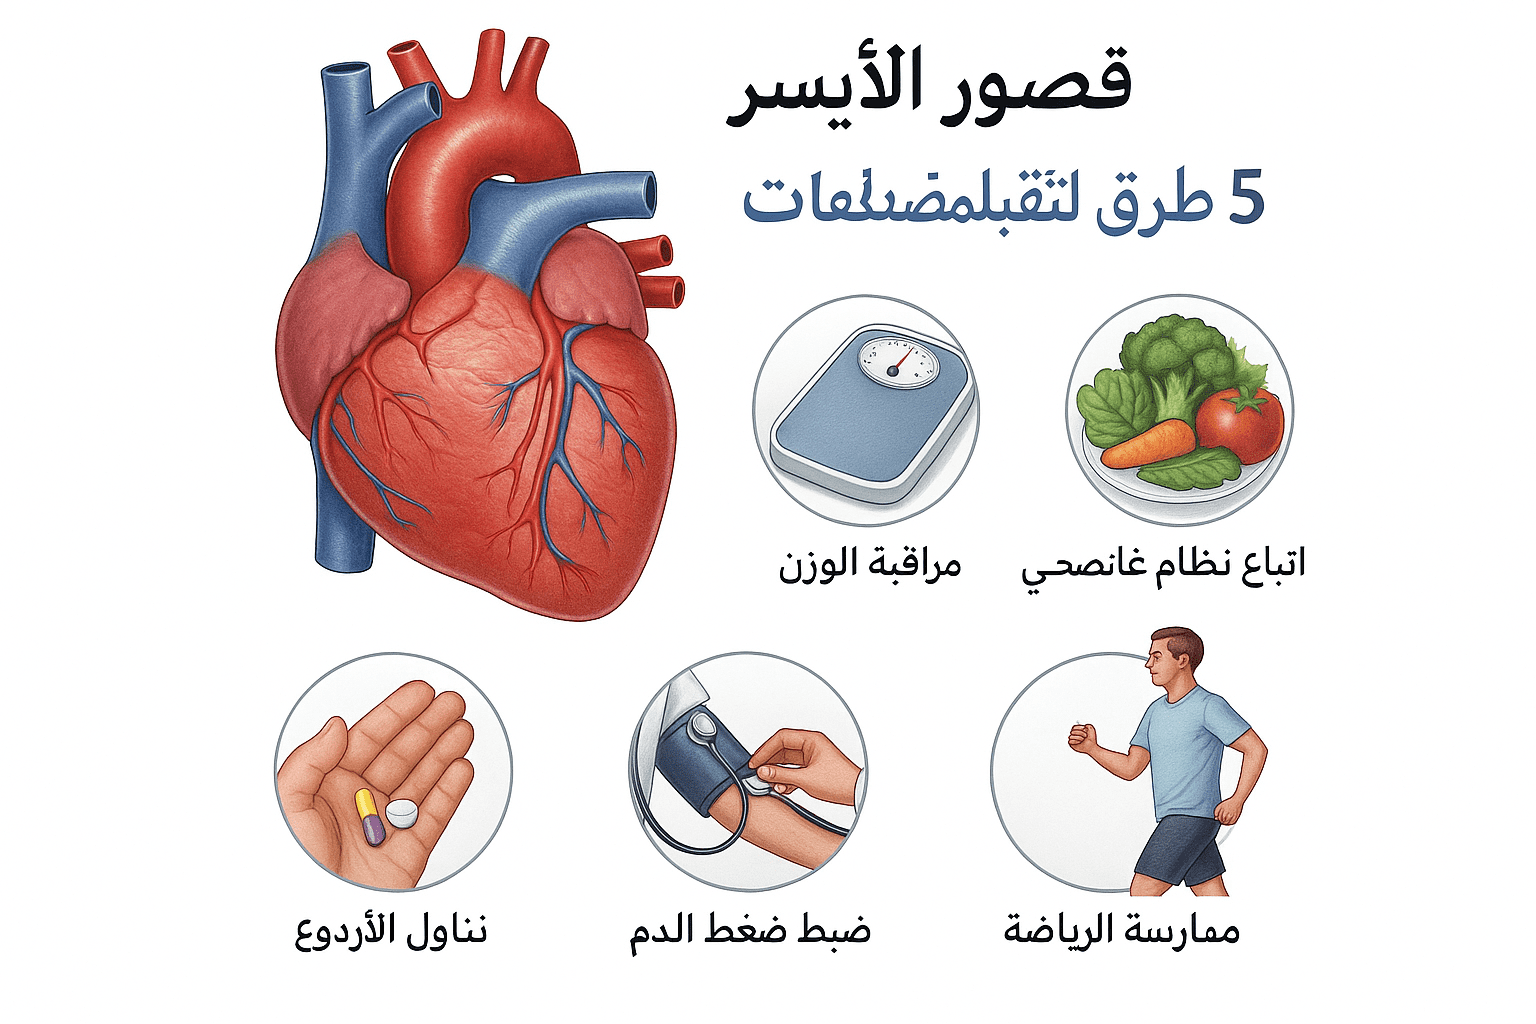

مقالات طبية من مساهمات الأطباء